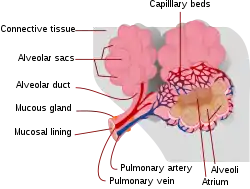

Respiratory zone

The conducting zone of the respiratory tract ends at the terminal bronchioles when they branch into the respiratory bronchioles. This marks the beginning of the terminal respiratory unit called the acinus which includes the respiratory bronchioles, the alveolar ducts, alveolar sacs, and alveoli.[29] An acinus measures up to 10 mm in diameter.[30] A primary pulmonary lobule is the part of the lung distal to the respiratory bronchiole.[31] Thus, it includes the alveolar ducts, sacs, and alveoli but not the respiratory bronchioles.[32]

The unit described as the secondary pulmonary lobule is the lobule most referred to as the pulmonary lobule or respiratory lobule.[27]: 489 [33] This lobule is a discrete unit that is the smallest component of the lung that can be seen without aid.[31] The secondary pulmonary lobule is likely to be made up of between 30 and 50 primary lobules.[32] The lobule is supplied by a terminal bronchiole that branches into respiratory bronchioles. The respiratory bronchioles supply the alveoli in each acinus and is accompanied by a pulmonary artery branch. Each lobule is enclosed by an interlobular septum. Each acinus is incompletely separated by an intralobular septum.[30]

The respiratory bronchiole gives rise to the alveolar ducts that lead to the alveolar sacs, which contain two or more alveoli.[22] The walls of the alveoli are extremely thin allowing a fast rate of diffusion. The alveoli have interconnecting small air passages in their walls known as the pores of Kohn.[22]

Respiratory tract

The lower respiratory tract is part of the respiratory system, and consists of the trachea and the structures below this including the lungs.[34] The trachea receives air from the pharynx and travels down to a place where it splits (the carina) into a right and left primary bronchus. These supply air to the right and left lungs, splitting progressively into the secondary and tertiary bronchi for the lobes of the lungs, and into smaller and smaller bronchioles until they become the respiratory bronchioles. These in turn supply air through alveolar ducts into the alveoli, where the exchange of gases take place.[34] Oxygen breathed in, diffuses through the walls of the alveoli into the enveloping capillaries and into the circulation,[22] and carbon dioxide diffuses from the blood into the lungs to be breathed out.